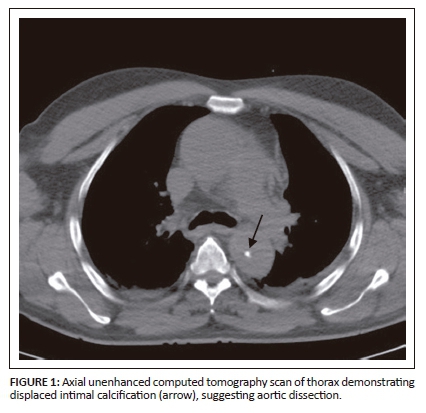

On unenhanced CT, intraluminal displacement of intimal calcifications can occasionally be seen, suggesting AD (Figure 1). A linear hypodense internally displaced structure representing the intimo-medial flap, separating the true and false lumens, is the most important CT finding seen in approximately 70% of cases (Figures 2, 5 and 8c).7 In the present era of endovascular management, differentiation of the true and false lumen is important in planning the management. The true lumen directly communicates with the aorta, and intimal calcifications, if present, surround it (Figure 3a). The calibre of the true lumen is smaller as compared to false lumen, which wedges around it owing to permanent systolic pressure. Fine linear scattered hypodense areas within the false lumen are termed the Cobweb sign (Figure 3a). It is specific for the false lumen and represents collagenous residual media fibres.8 The beak sign is another useful sign for the false lumen which represents a wedge of haematoma at the distal end of the false lumen on cross-sectional imaging (Figure 3b). It forms an acute angle between the dissection flap and vessel wall and represents the site of propagation.9 The false lumen shows less contrast enhancement compared to the true lumen in the early arterial phase and may appear hyperdense to the true lumen in the venous phase owing to contrast pooling (Figure 4).